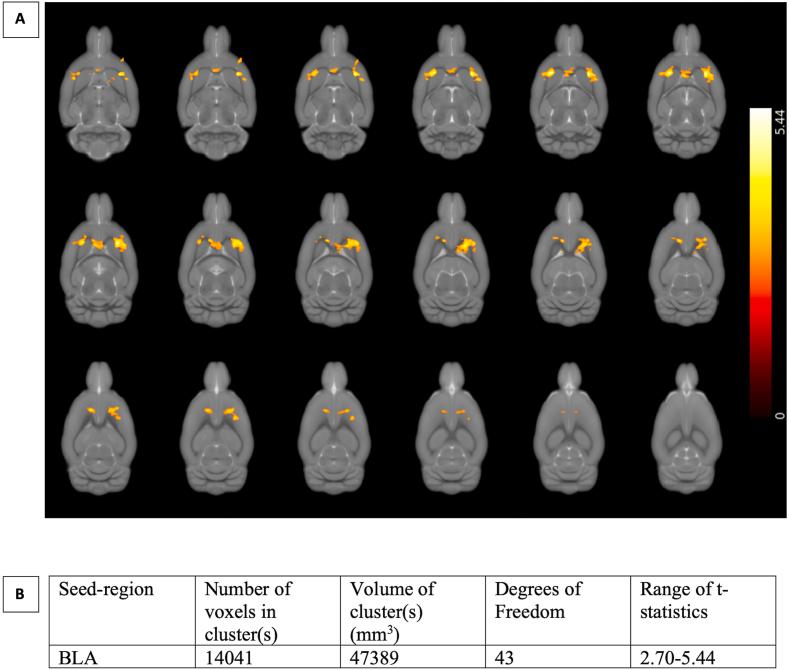

Major depressive disorder (MDD) is a stress-related condition hypothesized to involve aberrant reinforcement learning (RL) with positive and negative stimuli. The present study investigated whether repeated early maternal separation (REMS) stress, a procedure widely recognized to cause depression-like behaviour, affects how subjects learn from positive and negative feedback. The REMS procedure was implemented by separating male and female rats from their dam for 6 h each day from post-natal day 5-19. Control rat offspring were left undisturbed during this period. Rats were tested as adults for behavioral flexibility and feedback sensitivity on a probabilistic reversal learning task. A computational approach based on RL theory was used to derive latent behavioral variables related to reward learning and flexibility. To assess underlying brain substrates, a seed-based functional MRI connectivity analysis was applied both before and after an additional adulthood stressor in control and REMS rats. Female but not male rats exposed to REMS stress showed increased response 'stickiness' (repeated responses regardless of reward outcome). Following repeated adulthood stress, reduced functional connectivity from the basolateral amygdala (BLA) to the dorsolateral striatum (DLS), cingulate cortex (Cg), and anterior insula (AI) cortex was observed in females. By contrast, control male rats exposed to the second stressor showed impaired learning from negative feedback (i.e., non-reward) and reduced functional connectivity from the BLA to the DLS and AI compared to maternally separated males. RL in male rats exposed to REMS was unaffected. The fMRI data further revealed that connectivity between the mOFC and other prefrontal cortical and subcortical structures was positively correlated with response 'stickiness'. These findings reveal differences in how females and males respond to early life adversity and subsequent stress. These effects may be mediated by functional divergence in resting-state connectivity between the basolateral amygdala and fronto-striatal brain regions.

重度抑郁症(MDD)是一种与压力相关的疾病,据推测涉及对正负刺激的异常强化学习(RL)。本研究调查了反复早期母体分离(REMS)应激——一种被广泛认为会导致类似抑郁行为的程序——是否会影响受试者从正负反馈中学习的方式。REMS程序是通过在出生后第5天至19天每天将雄性和雌性大鼠与其母鼠分离6小时来实施的。在此期间,对照大鼠的后代未受干扰。成年后,对大鼠进行概率反转学习任务的行为灵活性和反馈敏感性测试。采用基于RL理论的计算方法来推导与奖励学习和灵活性相关的潜在行为变量。为了评估潜在的脑底物,在对照和REMS大鼠成年后施加额外应激源之前和之后,均应用基于种子的功能磁共振成像连接性分析。暴露于REMS应激的雌性而非雄性大鼠表现出反应“粘性”增加(无论奖励结果如何都会重复反应)。在成年后反复应激后,雌性大鼠中观察到从基底外侧杏仁核(BLA)到背外侧纹状体(DLS)、扣带回皮质(Cg)和前岛叶(AI)皮质的功能连接减少。相比之下,与母体分离的雄性大鼠相比暴露于第二个应激源的对照雄性大鼠从负反馈(即无奖励)中学习受损,并且从BLA到DLS和AI的功能连接减少。暴露于REMS的雄性大鼠的RL未受影响。功能磁共振成像数据进一步显示,内侧前额叶皮质(mOFC)与其他前额叶皮质和皮质下结构之间的连接性与反应“粘性”呈正相关。这些发现揭示了雌性和雄性对早期生活逆境和随后应激反应的差异。这些影响可能由基底外侧杏仁核与额纹状体脑区之间静息态连接性的功能差异介导。